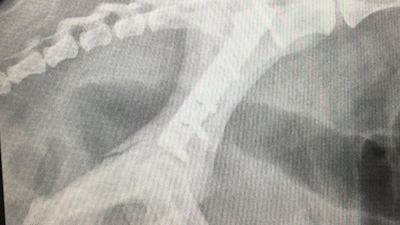

Soft Tissue Sarcoma

2 attempted removals by referring vet. Regrowth within 2 weeks.